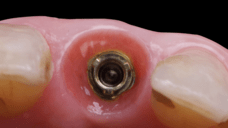

On the same day as the surgery, an immediate-load provisional crown was delivered. This restoration was fabricated in acrylic resin and screw-retained on the implant, following the “one abutment one time” principle. The provisional crown was carefully adjusted to avoid occlusal loading while supporting the peri-implant soft tissue architecture during the healing phase.

The provisional not only satisfied the patient’s functional and esthetic demands but also played a key role in shaping the emergence profile and conditioning the gingival margin. By providing a provisional solution immediately, the patient was able to leave the clinic with a natural-looking smile, avoiding any psychological or social impact associated with tooth loss in the anterior maxilla.